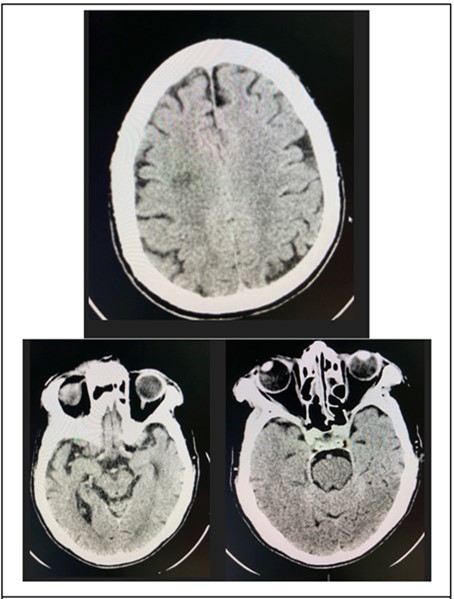

At the emergency room of the tertiary hospital, the patient had persistence of the diplopia and dizziness. The initial impression at that time was Cerebrovascular Infarct, thus a Plain Cranial CT Scan was done (conducted 6 hours after the onset of symptoms), which revealed a hypodense focus in the sub-cortical region of the right centrum semiovale extending to the right corona radiata, orbits, midbrain and pons were all normal. (Figure 2 and Figure 3)

Figure 4.Cranial CT Scan plain, axial of the patient done 6 hours after onset of diplopia, shows a hypodense focus in the sub cortical region of the right centrum semiovale extending to the right corona radiata

Cranial CT Scan plain, axial of the patient done 6 hours after onset of diplopia, shows a hypodense focus in the sub cortical  region of the right centrum semiovale extending to the right corona radiata

Figure 5.Cranial CT Scan plain, axial with orbital cuts of the patient which shows un remarkable orbit, midbrain and pons findings.

Cranial CT Scan plain, axial with orbital cuts of the patient which shows un remarkable orbit, midbrain and pons findings.